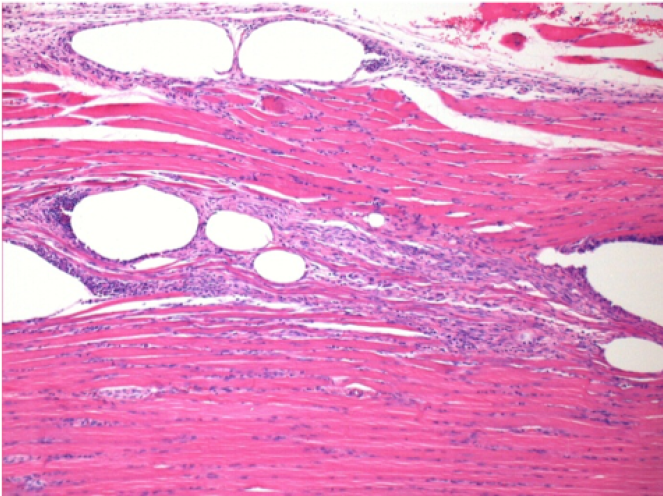

3 meses después de la inyección de Endopeel

3 meses (D90) después de la inyección de Endopeel 0.1ml en el músculo pretibial derecho.

L : Control-100xD90

R:100xD90